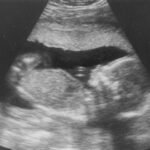

Oligohydramnios Definition Oligohydramnios is an abnormal condition occurring during pregnancy resulting from lack of amniotic fluid (fluid surrounding the baby in the uterus) [1]. This fluid plays a vital role in proper fetal development while its deficiency can lead to oligohydramnios sequence or Potter sequence characterized by an irregular appearance of … [Read more...] about Oligohydramnios